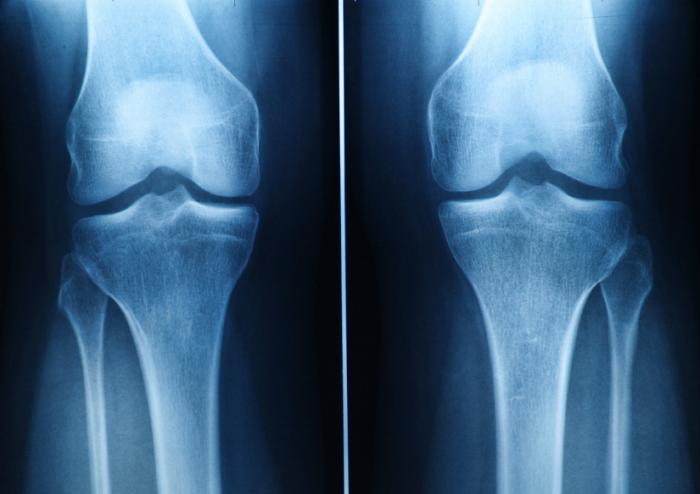

Understanding Cartilage and Its Damage

Cartilage is crucial for joint function, providing cushioning and flexibility. Damage, whether from trauma or conditions like osteoarthritis, reduces its effectiveness.